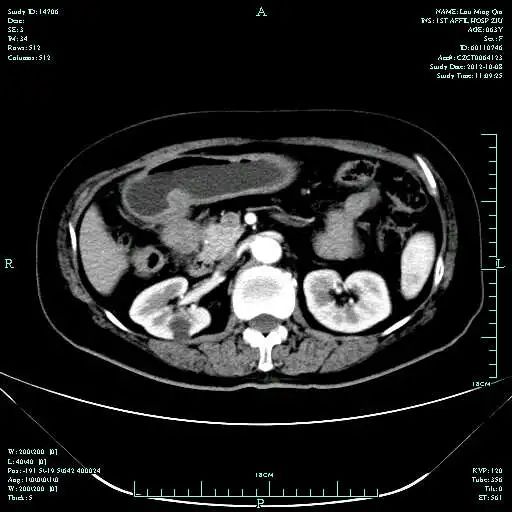

CT-T

CT-H1

MR-H1

影像学检查结果评估:cPD。